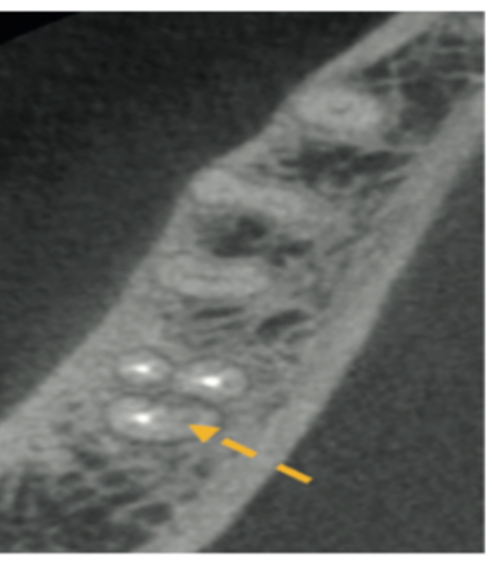

9) Identify which canal of tooth 47 was not obturated (indicated by orange arrow).